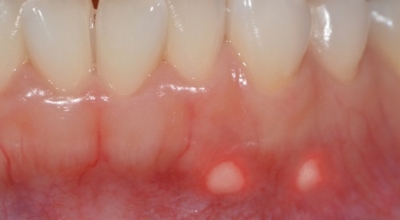

바이러스로 인해 나타나는 구내염도 있습니다. 단순 헤르페스 바이러스의 감염 원인의 '헤르페스성 구내염'은 주로 타액 과 같은 접촉으로 인하여 감염됩니다. 또 곰팡이의 일종인 칸디다균은 원래 입안에 존재하는 상재균의 한 개지만, 만약 면역력이 저하되면 증식해서 '칸디다성 구내염'을 병이 발생하게 되어요. 바이러스성 구내염에 많이 관찰되는 다발성 구내염은 입 점막에 많은 소수포가 형성되어 찢어져 붕괴를 나타나게 할 수이 있고 발열이나 엄청난 통증이 수반될 수 있습니다.